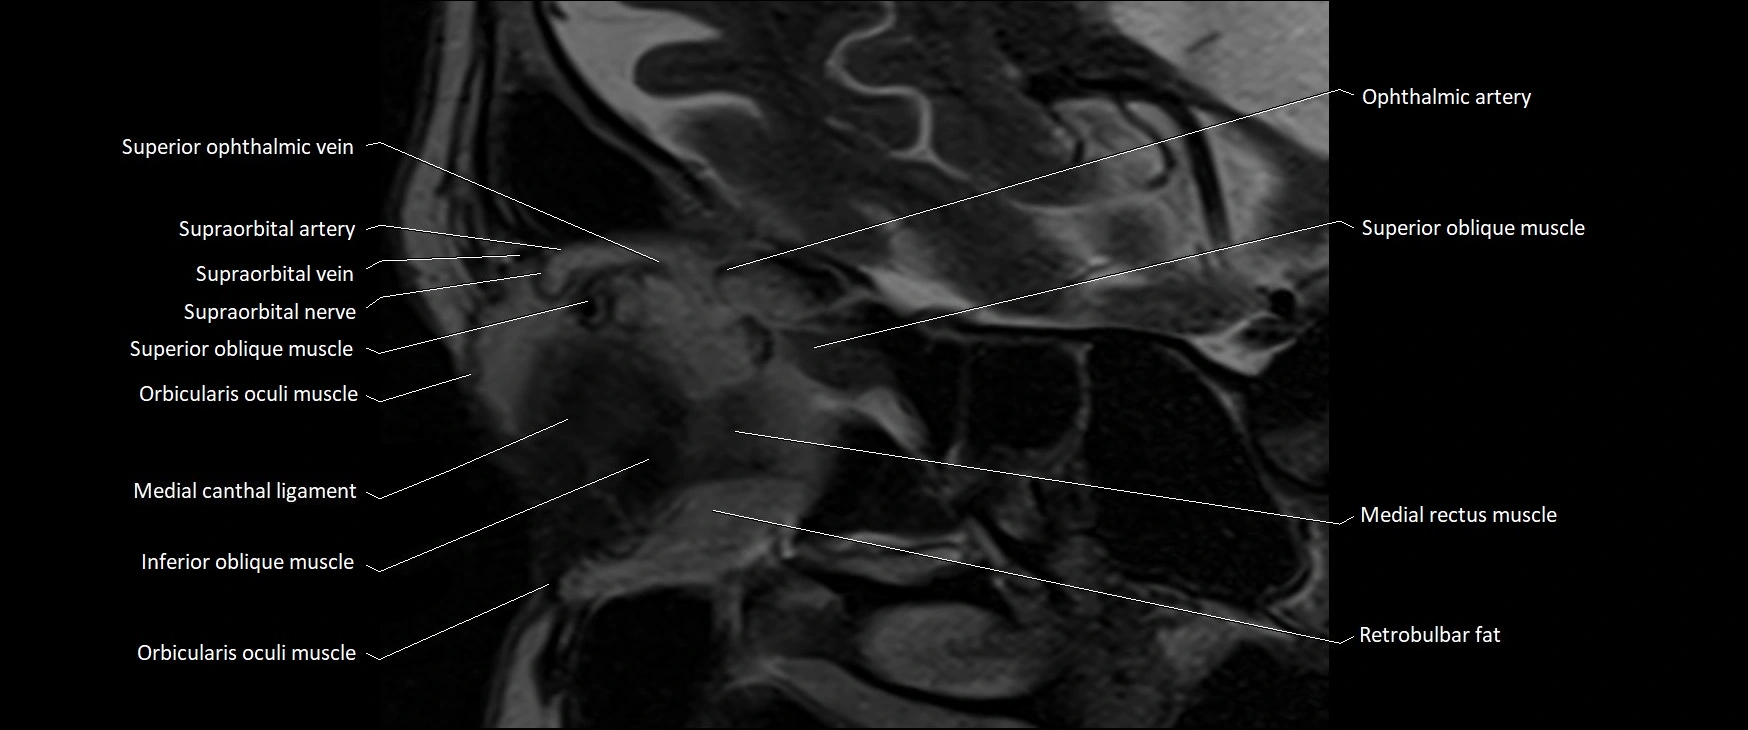

MRI images